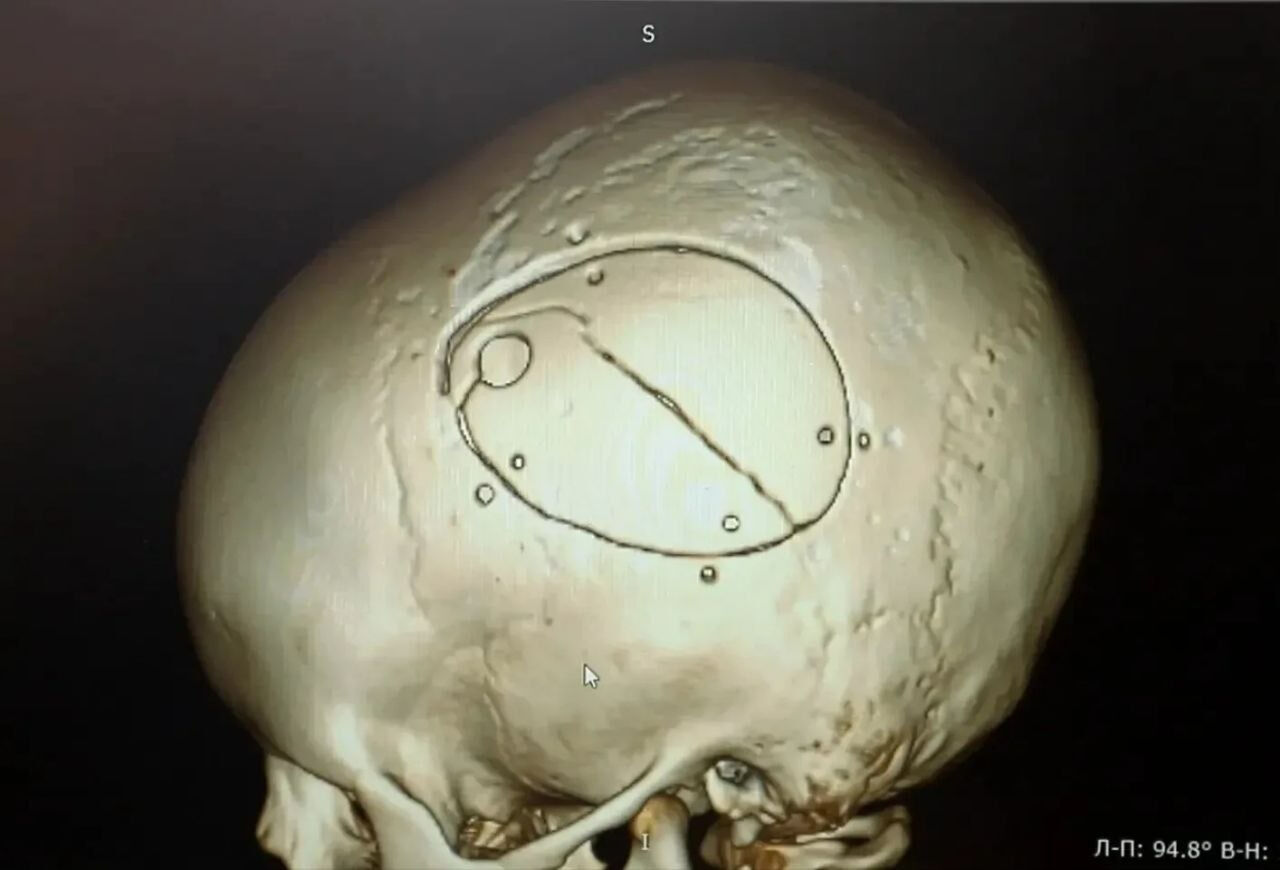

Как сообщает Минздрав Кузбасса, сразу после происшествия у ребёнка не было видимых травм головы, однако на следующий день он начал отказываться от еды. Родители обратились в больницу, где обследование выявило серьёзные повреждения – перелом черепа и острую эпидуральную гематому.

Мальчика экстренно доставили в операционную. Нейрохирурги провели сложную операцию – костно-пластическую трепанацию черепа, удалили гематому и остановили кровотечение.